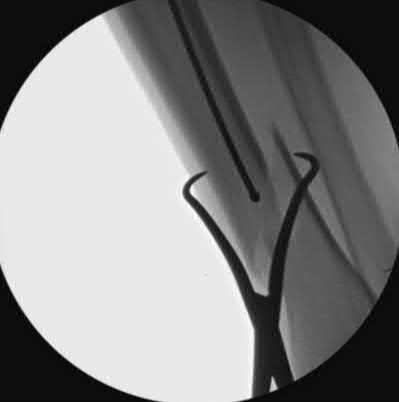

A 25-year-old female is involved in a motor vehicle collision. She presents with the isolated injury seen in Figures A through D. Her leg is swollen but her skin is intact. She has no clinical signs of compartment syndrome. Which of the following treatment options will allow for maintenance of fracture alignment and minimize the risk of soft tissue complications?

The patient presents with a closed distal third metaphyseal-diaphyseal distal tibia fracture with simple intra-articular extension. Immediate intramedullary nailing along with percutaneous fixation of the articular component provides appropriate restoration of length, rotation and alignment and minimizes the risk of wound complication.

Displaced distal third tibia fractures may be associated with simple intraarticular extension. Operative treatment of intra-articular distal tibia fractures has historically been performed with open reduction and internal fixation. Early open reduction and plate fixation of pilon fractures has been associated with high rates of infection and wound complication. In select patterns with simple articular extension, percutaneous screw fixation and medullary nailing may provide appropriate reduction with minimal soft-tissue risk.

Figures A and B demonstrate a distal third tibial shaft fracture with simple intra-articular extension. The axial and coronal CT cuts in Figures C and D further clarify the articular injury. Illustrations A and B demonstrate a comminuted distal third tibial fracture with simple intra-articular extension. Illustrations C and D are fluoroscopic images of the same injury after intramedullary nailing and percutaneous fixation of the articular component.